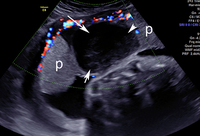

Descolamento da placenta

Imagem de ultrassonografia de descolamento da placenta: a placenta normal está marcada com 'p'; área de descolamento indicada por setas brancas

Do acervo de Dr Y Oyelese; usado com permissão